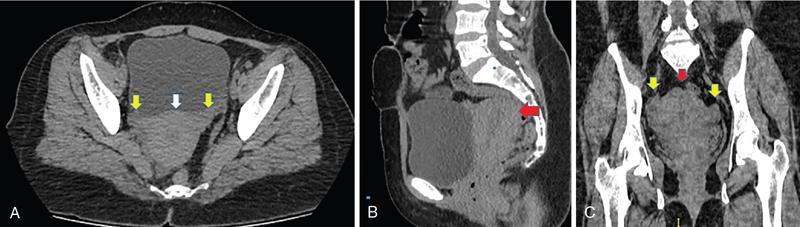

IMAGING ANATOMY OF MALE REPRODUCTIVE SYSTEM Ganesh Rajagopal The male reproductive system is formed by testes, ejaculatory ducts, seminal vesicles (SVs), prostate and penis. Various diagnostic imaging modalities like ultrasound (US), computed tomography (CT), magnetic resonance imaging (MRI) and positron emission tomography (PET) are helpful in the diagnostic evaluation of male reproductive system. Various indications for imaging may include acute scrotum (testicular torsion, trauma and epididymo-orchitis), scrotal swelling (hydrocele, spermatocele, idiopathic scrotal wall oedema and scrotal abscess) and infertility. US and MRI are the commonly used imaging modalities in male reproductive system which complement each other. CT is not very useful due to poor contrast resolution. Ultrasound imaging (US) with a high-frequency linear (7.5–10 MHz) transducer probe has become the imaging modality of choice for scrotal evaluation. Scrotal US is an excellent imaging modality as it can demonstrate abnormalities in testis as well as in paratesticular structures. Scrotal wall is formed by the skin, superficial fascia, dartos muscle, the external spermatic fascia, cremasteric fascia and the internal spermatic fascia. The scrotum is divided into two cavities by a median raphe. This multilayered scrotal wall is poorly delineated in US and MRI, it is typically hypointense on both T1- and T2-weighted images. Testes are paired organs, located normally in scrotal sac, suspended by the spermatic cords. Each testis is examined in orthogonal transverse and longitudinal planes, with both grey scale and colour Doppler modes, to assess its volume and blood flow. Volume of testis is calculated by length × height × width × 0.71. A total volume (both testes) of >30 mL and a single testicular volume of 12–15 mL is generally considered normal for adults. Testes are supplied by the testicular arteries, which arise from the aorta and enter the spermatic cord at deep inguinal ring to reach the upper pole of testis. Pampiniform plexus of veins surrounds the testis and appears as a serpiginous tubular structure posterior to it, measuring >2–3 mm in diameter. Testes are oval shaped, with homogeneous echotexture on grey scale US. Along with the epididymis, they are surrounded by an echogenic capsule, known as the tunica albuginea. Tunica albuginea is covered by tunica vaginalis, which is a remnant of the processus vaginalis and both represent closed sac of peritoneum with two layers. This tunica albuginea is seen extending into posteromedial testis and form the mediastinum testis (Fig. 11.2.1.1), which consists of ducts, nerves and blood vessels. The mediastinum testis is seen as a thin echogenic band. Rete testis is formed by the convergence of seminiferous tubules, seen as a hypoechoic area adjacent to mediastinum testes. The epididymis is a comma-shaped, elongated structure placed at the posterior border of the testis, which drains the efferent ductules (Fig. 11.2.1.2). It has head, body and tail. The head overlies the superior pole of the testis and is isoechoic or slightly hyperechoic whereas, the body and tail are located behind and along the inferior pole and are usually isoechoic. The tail of the epididymis continues into vas deferens (VD), which along with the nerves, lymphatic and vascular structures, forms the spermatic cord (Fig. 11.2.1.3). The spermatic cord appears as an echogenic band in the inguinal canal. The normal adult testis is a homogeneous oval structure that appears hyperintense on T2-weighted sequences and hypointense–isointense on T1-weighted images (Fig. 11.2.1.4). The tunica which surrounds the testis is hypointense T1- and T2-weighted sequences. Epididymis is isointense on T1-weighted images but hypointense on T2-weighted images compared to testis (Fig. 11.2.1.5). Both testicles and epididymis enhance after intravenous administration of gadolinium (Gd) MR contrast agents. Prostate, though visualized by transabdominal scan is better assessed by transrectal high frequency (7.5–10 MHz) ultrasound transducer (TRUS) with patient in left lateral decubitus position. The prostate gland is divided into the anterior fibromuscular stroma (devoid of glandular tissue), transition zone, central zone, periurethral zone and peripheral zone. The base of the prostate is located superiorly and contiguous with the bladder neck whereas, the apex of the prostate is located at the inferior aspect continuous with the striated muscles of the urethral sphincter. The neurovascular bundle is seen to course near the posterolateral aspect of prostate, which is a preferential route of tumour spread. The prostate appears as a cone-shaped organ and shows uniform low echogenicity (Fig. 11.2.1.6). The outer gland (central and peripheral zones) is generally more echogenic than the inner gland. The transition and central zones of the prostate have similar MR signal intensity and cannot be differentiated, hence, are collectively referred as the central gland. On T2-weighted MR images, the normal peripheral zone is homogeneously hyperintense, whereas the central gland tissue is typically hypointense or isointense compared to the skeletal muscle (Fig. 11.2.1.7). The capsule and the anterior fibromuscular stroma appear hypointense on T2-weighted MR images. The SVs are seen as septate tubular cystic structures, appearing uniformly anechoic in US, above the prostate with distal portion of VD is seen medial to it. The duct of SV and VD joins to form the ejaculatory duct, which drains into the prostatic urethra via verumontanum. SVs show ‘bow-tie’ appearance in transversal scans, and a club or tennis-racket shape in longitudinal scans (Fig. 11.2.1.8). On MR, SVs are seen as elongated fluid-containing structures with thin septa, which is hypointense on T1 and hyperintense on T2-weighted MR images (Fig. 11.2.1.9). The VD is seen as a tubular structure with low signal intensity in both T1- and T2-weighted images, on either side. The dilated distal portion of VD (ampulla), appears hyperintense on T2-weighted images, similar to that of the SV due to the fluid content (Fig. 11.2.1.10). The penis, being a superficial organ, is usually examined with US, although MRI is reserved as problem solving modality. The penile body contains two paired muscles – corpora cavernosa and a corpus spongiosum. The former performs as a main erectile body while the latter contains the penile urethra (Fig. 11.2.1.11). Dartos fascia forms the outer layer and the Buck fascia forms the inner layer, which contain the deep dorsal vein (DDV) and a paired dorsal neurovascular bundle. The corpus spongiosum and corpora cavernosa are of high signal intensities on T2-weighted MR images and intermediate-low signals on T1-weighted MR images. The tunica albuginea being a fibrous sheath, surrounds all the three muscles, is hypointense on all sequences (Fig. 11.2.1.12). IMAGING ANATOMY OF FEMALE REPRODUCTIVE SYSTEM Saranya The female reproductive system comprises of uterus, cervix, fallopian tubes, ovaries, vagina and vulva. Ultrasonography (transabdominal and transvaginal) is the primary imaging modality of choice for imaging the female pelvis. Computed tomography (CT) is less often used for pelvic imaging. It provides a quick and systematic overview with coverage of the abdomen in the same session. Hence, CT is well suited for staging pelvic cancers and for imaging gynaecologic and nongynaecologic diseases presenting with acute abdominal pain. Pelvic anatomy is well demonstrated by magnetic resonance imaging (MRI). The contrast resolution of T2-weighted images form the basis for superb tissue characterization of MRI. Uterus is a thick-walled fibromuscular organ composed of myometrium and endometrium. It has two major divisions, namely, the body (corpus) and cervix. The fundus lies above the ostia of fallopian tubes. The normal uterus measures between 5 and 9 cm in length and is in an anteverted position, in relation to the urinary bladder. The myometrium shows three layers on USG, a compacted thin, hypoechoic inner layer forms subendometrial halo, a thicker, homogenously echogenic middle layer and a thinner, hypoechoic outer layer (peripheral to arcuate vessels). The appearance of the endometrium varies with the phase of the menstrual cycle. It appears as a thin echogenic line early in the proliferative phase and shows hypoechoic thickening (4–8 mm) as proliferative phase progresses. It shows a triple layer (sandwich or trilaminar) appearance in the mid cycle and may measure up to 12–16 mm. During secretory phase after ovulation, the layers are seen hyperechoic due to the increasing complexity of glandular structure and secretions (Fig. 11.2.2.1). Postmenopausally, the endometrium decreases in thickness. Endometrial thickness of 5 mm is taken as cut-off. Women on hormonal therapy acceptable endometrial thickness is up to 8 mm. Three-dimensional US permits multiple views to be reconstructed from a single sweep through the uterus. Sonohysterogram is the study of choice for detailed evaluation of the endometrial cavity pathologies. The cervix begins at the inferior narrowing of the uterus (isthmus) at the internal os, which is identified by the entrance of uterine vessels. It has supravaginal and vaginal portions. It is 3–4 cm long and shortens after childbirth. In premenarche women, cervix is larger than corpus, forming approximately 2/3 of the uterine mass. During menarche, there is preferential growth of the corpus and in nulliparous women, corpus and cervix are roughly equal, whereas in parous woman, corpus forms approximately 2/3 of the uterine mass. Uterus is an extraperitoneal organ. The peritoneum extends over urinary bladder dome to anterior uterus, forming anterior cul-de-sac (vesicouterine pouch) and posteriorly, the peritoneum extends more inferiorly to the upper portion of vagina, forming the posterior cul-de-sac (pouch of Douglas, rectouterine pouch), which forms the most dependent portion of the female pelvis. Supporting ligaments of the uterus comprise mainly of broad ligaments, which extend laterally to the pelvic wall and round ligaments, which arise from uterine cornu near fallopian tubes to course anteriorly, pass through the inguinal canal to insert on the labia majora. Connective tissue thickening at the base of the broad ligament forms the uterosacral ligaments posteriorly, cardinal ligaments laterally and vesicouterine ligaments anteriorly. CT examination displays the uterus as a triangular or ovoid soft tissue structure behind the urinary bladder (Fig. 11.2.2.2). Following the administration of intravenous contrast, there is enhancement of myometrium that helps to delineate the endometrium. The vagina, cervix and corpus can be differentiated by morphological characteristics and enhancement pattern. The uterine corpus is typically triangular, whereas cervix is more rounded. The vagina has an appearance of flat rectangle at the level of fornix. The broad ligament and round ligaments are seen coursing laterally and anteriorly, respectively. The main source of vascular supply to uterus is from the uterine arteries. The uterine arteries pass within the broad ligament to enter the uterus, adjacent to the lateral fornices. The uterine artery passes over the ureter at the level of the cervix. Then it courses superiorly, along the lateral margin of the uterus and anastomoses with the ovarian artery. Uterine arteries give rise to arcuate arteries, which run in the outer third of myometrium. Radial arteries extend through the myometrium, which terminate as spiral arteries in the endometrium. The venous system parallels the arterial system, forms a complex venous network in the parametrium and drains to the iliac veins. Middle and lower thirds of the uterus are drained by obturator, parametrial and paracervical lymph nodes. Lymphatic drainage from the upper corpus and fundus goes to the common iliac and paraaortic lymph nodes. MRI provides a more comprehensive view of the uterine anatomy. On MRI, the uterus and cervix show uniform low to intermediate signal on T1-weighted images. On T2-weighted images, uterus shows three distinct zones, namely high signal endometrium, low signal junctional zone and intermediate signal myometrium (Fig. 11.2.2.3). The normal thickness of the junctional zone varies from 2 to 8 mm. A thickness of 9 to 12 mm is equivocal and greater than 12 mm is abnormal. Both endometrium and junctional zone become thin with oral contraceptive intake. Endometrial atrophies and the junctional zone is absent in postmenopausal women. The endocervical canal shows high signal on T2-weighted images, whereas cervical stroma shows low signal, contiguous with the junctional zone. An outer layer of intermediate signal smooth muscle is present. Nabothian cysts representing obstructed, mucous secreting glands are commonly seen as low signal on T1-weighted images and high signal on T2-weighted images. Parametrium shows low to intermediate signal intensity on T1-weighted images and variable signal intensity on T2-weighted images. The round ligaments and uterosacral ligaments show low signal intensity, cardinal ligaments and associated venous plexuses show high signal intensity on T2-weighted images. Ovaries are located posterolateral to the body of the uterus between the uterus and the pelvic sidewall. The internal iliac vessels lie immediately posterior to the ovary. Exact position is variable due to the laxity in the ligaments, parity, uterine size and position. On USG, medulla of the ovaries is mildly hyperechoic compared to the hypoechoic cortex. Developing follicles appear anechoic (Fig. 11.2.2.4). Corpus luteum may have a thick, echogenic ring and haemorrhage is common.